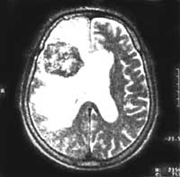

РАК ВИДЕН ДАЖЕ В ВОЗДУХЕ

Почему с каждым годом все больше людей становятся жертвами злокачественных опухолей? На этот вопрос можно дать десятки ответов, но ни для кого не является секретом тот факт, что в значительной степени проблема роста заболеваемости раком связана с трудностями, возникающими при диагностике этой болезни.

Очередной разработкой, вызвавшей бурные восторги специалистов, стал метод экспресс-диагностики рака легких, предложенный учеными из Университета Глазго. В отличие от стандартных диагностических тестов, основанных на микроскопии ткани легких или сложных рентгенографических исследованиях, в его основу положен… анализ выдыхаемого человеком воздуха. Дело в том, что развитие любой злокачественной опухоли всегда сопровождается активным распадом клеток, а при распаде клеток выделяется газ этан (не образующийся ни при каких других биохимических процессах). Соответственно, измерив его содержание в выдыхаемом человеком воздухе, можно сделать выводы о наличии у него рака легких, а также примерно оценить размеры и стадию злокачественной опухоли. Причем, что интересно, предназначенный для этой цели прибор вовсе не является "чудом техники" - подобные аппараты, хотя и обладающие меньшей разрешающей способностью, уже давно используются в нефтегазовой промышленности.